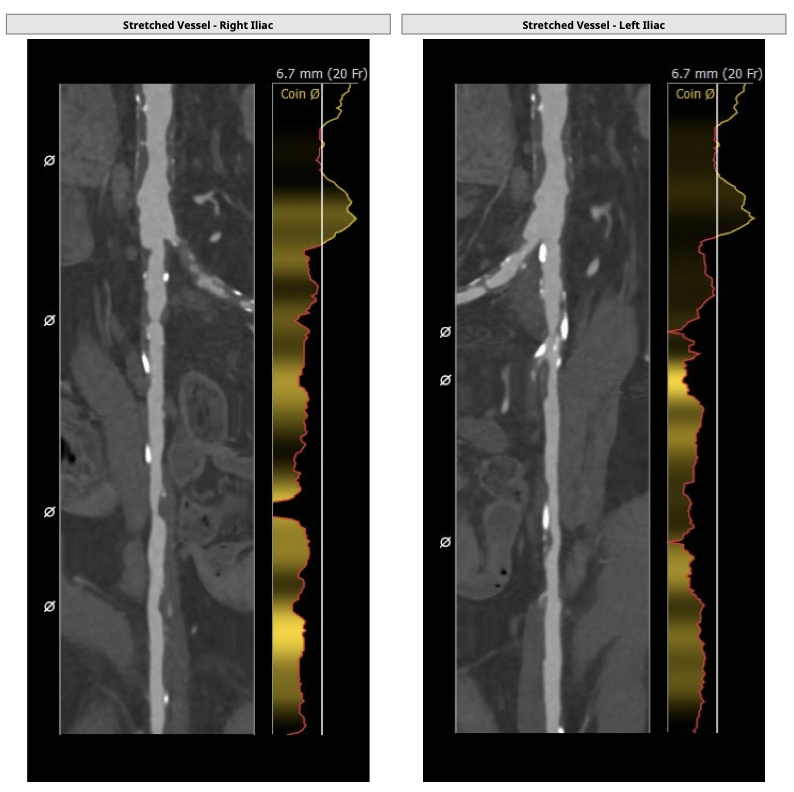

①患者因规律透析导致钙磷代谢紊乱,外周血管斑块钙化严重,最狭窄处仅2.8mm,通路建立难度极大(左右颈动脉均不符合入路条件);

确保冠脉安全,拟采取PCI+TAVR一站式手术策略,因患者右侧股动脉钙化严重、入路狭窄,拟采取无鞘法从右股动脉穿刺入路,选用20mm球囊预扩、L23号VenusA-Valve瓣膜、采用VenusA-Plus输送系统确保瓣膜的精确释放,瓣膜释放后结合造影和超声情况,决定是否后扩。